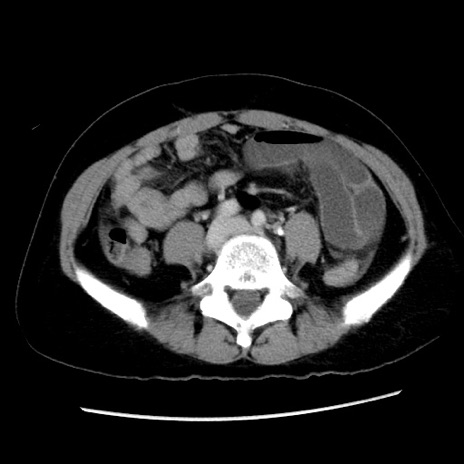

症例10(横断像)

【症例】 50歳代女性

【主訴】 腹痛

【現病歴】前日生レバーを食べた。今朝に排便あり。 昼前に突然発症の腹痛を生じ、当院救急外来を受診した。

【既往歴】 子宮筋腫にてで子宮全摘後

【身体所見】 意識清明、腹部:平坦、軟、下腹部やや左を中心に圧痛・反跳痛あり、筋性防御あり

【データ】WBC 7800、CRP 0.07